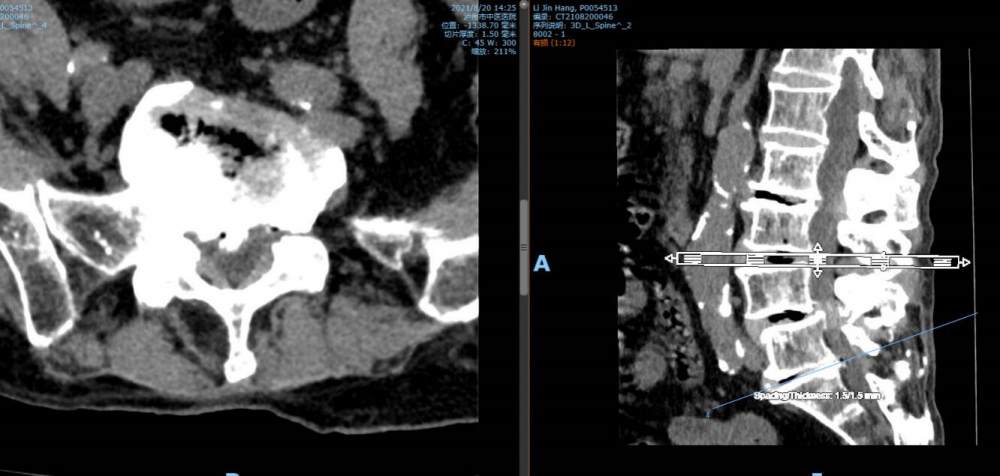

腰4 5椎間盤CT

腰5 骶1椎間盤CT